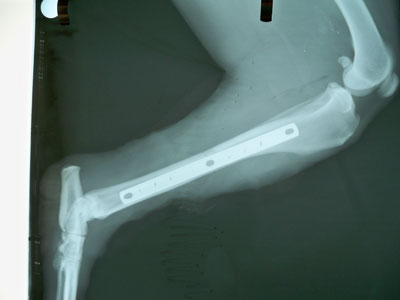

Μεγαλόσωμος σκύλος 30kg 1 έτους με τέλειο κάταγμα μεσότητας διάφυσης δεξιάς κνήμης.Το χειρουργείο πραγματοποιήθηκε στις 06/10/09.

Μεταλλική πλάκα 3,5mm τοποθετήθηκε στην έσω επιφάνεια της κνήμης με 8 κοχλίες 3,5mm.